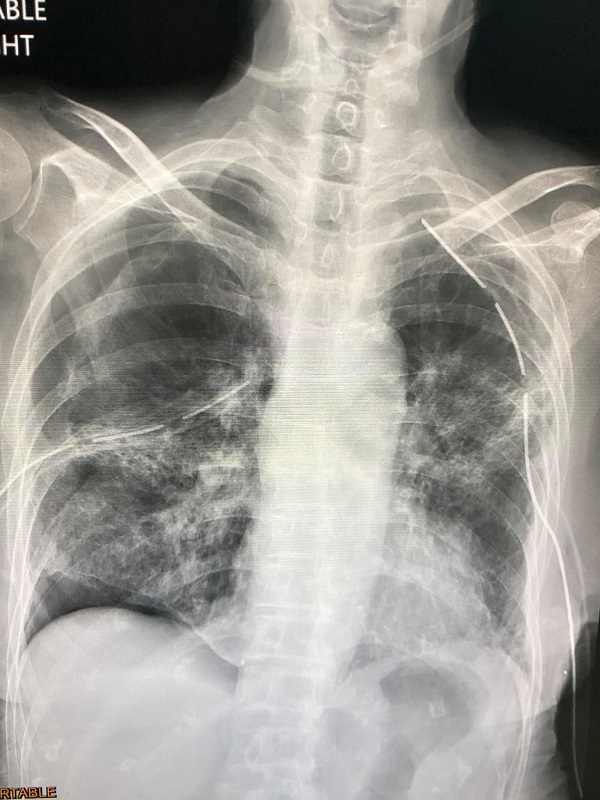

ผู้ป่วยหญิงไทยอายุ 77 ปี ไม่สูบบุหรี่ ปกติแข็งแรง ไม่มีปัญหาทางปอด ยังไม่ได้ฉีดวัคซีนป้องกันโรคโควิด วันที่ 8 กรกฎาคม 2564 มีไข้ ไอ เหนื่อย ปอดอักเสบทั้ง 2 ข้างจากโรคโควิด-19 ได้รับการรักษาด้วยยาและออกซิเจน ไม่ได้ใส่เครื่องช่วยหายใจ 22 วันหลังเริ่มป่วย

วันที่ 30 กรกฎาคมเหนื่อยมากขึ้นจากปอดข้างซ้ายรั่วเอง ต้องใส่ท่อระบายลม ถอดท่อระบายลมออก วันที่ 9 สิงหาคม ปอดอีกข้างรั่วเอง วันที่ 18 สิงหาคม ต้องใส่ท่อระบายลม วันที่ 23 สิงหาคม ปอดข้างซ้ายรั่วอีก ต้องใส่ท่อระบายลมอีกครั้ง วันที่ 28 สิงหาคม ถอดท่อระบายลมข้างซ้าย วันที่ 31 สิงหาคม ปอดข้างซ้ายรั่วอีก ต้องใส่ท่อระบายลมครั้งที่ 3 วันที่ 2 กันยายน ทำคอมพิวเตอร์สแกนปอดพบพังผืดทั่วปอดร่วมกับหลอดลมเล็กๆโป่งพอง

วันที่ 10 กันยายน ได้ทำการผ่าตัดปอดข้างขวาเพราะปอดขวาไม่ขยายตัวเต็มที่ ด้วยการส่องกล้องเข้าไปในช่องทรวงอกข้างขวา พบถุงลมพองโตที่ผิวของยอดปอดข้างขวาด้านบนและด้านล่าง ต้องตัดปอดเฉพาะส่วนนั้นและเย็บปิด ตัดเยื่อหุ้มปอดด้านขวา ใส่แป้ง Talc เข้าช่องปอดขวา และผ่านท่อระบายลมข้างซ้าย เพื่อให้เยื่อหุ้มปอดข้างขวาและซ้ายติดกัน และส่งชิ้นเนื้อปอดตรวจทางพยาธิวิทยาพบ เนื้อปอดถูกทำลาย มีทั้งอักเสบและพังผืดทั่วไป มีถุงลมพองในเนื้อปอด ขณะนี้ยังต้องใส่ท่อระบายลมทั้งสองข้าง